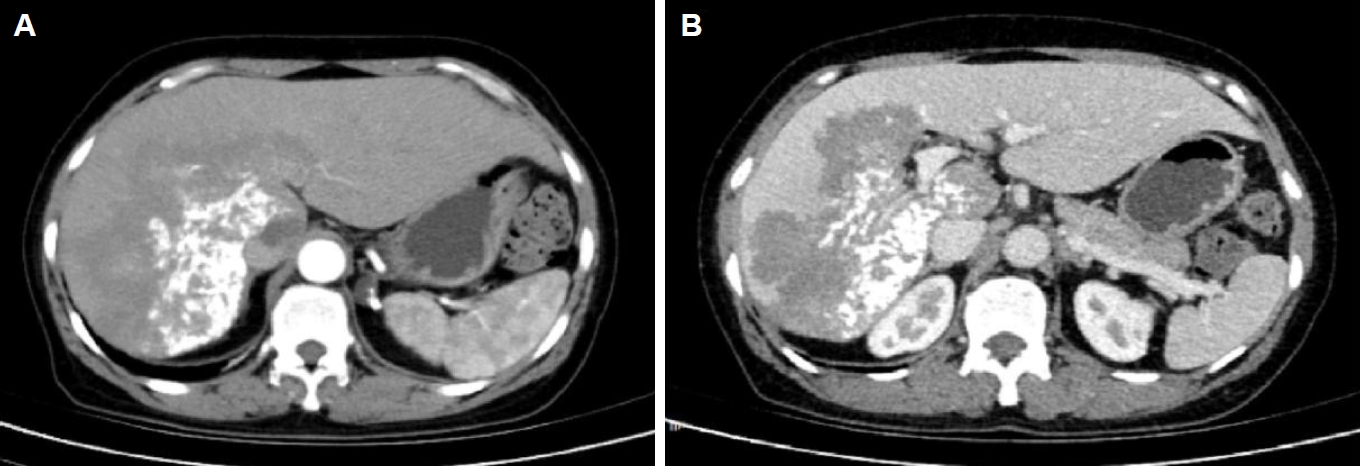

Magnetic resonance imaging showed irregular, slightly hyperintense T1 signals in the right lobe and caudate lobe (14.5×9.6×11.5 cm) without enhancement. The capsule showed enhancement, with inferior vena cava locally compressed. Diffusion-weighted imaging revealed slightly high signals (Fig. 3). T2-weighted imaging showed irregular, slightly hyperintense T2 signals in the right lobe and caudate lobe, with high diffusion-weighted imaging signals. A round, hyperintense T2 lesion (1.6×1.3 cm) was seen in the left adrenal gland (Fig. 4A, B). The absence of typical multilocular cystic structures cannot rule out HAE, as the disease may present as a solid, pseudotumoral mass with central necrosis and peripheral fibrosis, especially in endemic areas.

Fig. 3.

Magnetic resonance imaging demonstrates a large area of mildly prolonged T1 signal within the liver parenchyma, showing no enhancement post-contrast, with slightly hyperintense signal on diffusion-weighted imaging.

Fig. 4.

(A) Magnetic resonance imaging T2-weighted imaging demonstrates mildly prolonged T2 signal in the right hepatic lobe and caudate lobe. (B) A round-shaped, hyperintense T2 signal lesion is observed in the left adrenal gland, which also shows high signal intensity on diffusion-weighted imaging.

Fig. 3. Magnetic resonance imaging demonstrates a large area of mildly prolonged T1 signal within the liver parenchyma, showing no enhancement post-contrast, with slightly hyperintense signal on diffusion-weighted imaging.

Fig. 4. (A) Magnetic resonance imaging T2-weighted imaging demonstrates mildly prolonged T2 signal in the right hepatic lobe and caudate lobe. (B) A round-shaped, hyperintense T2 signal lesion is observed in the left adrenal gland, which also shows high signal intensity on diffusion-weighted imaging.